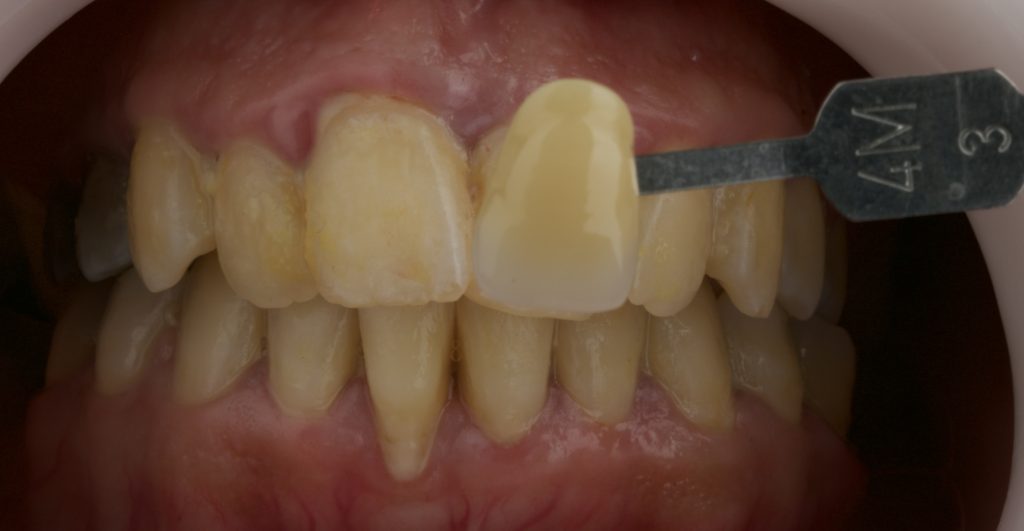

- Initial tooth shade: 4M3 (VITA shade guide).